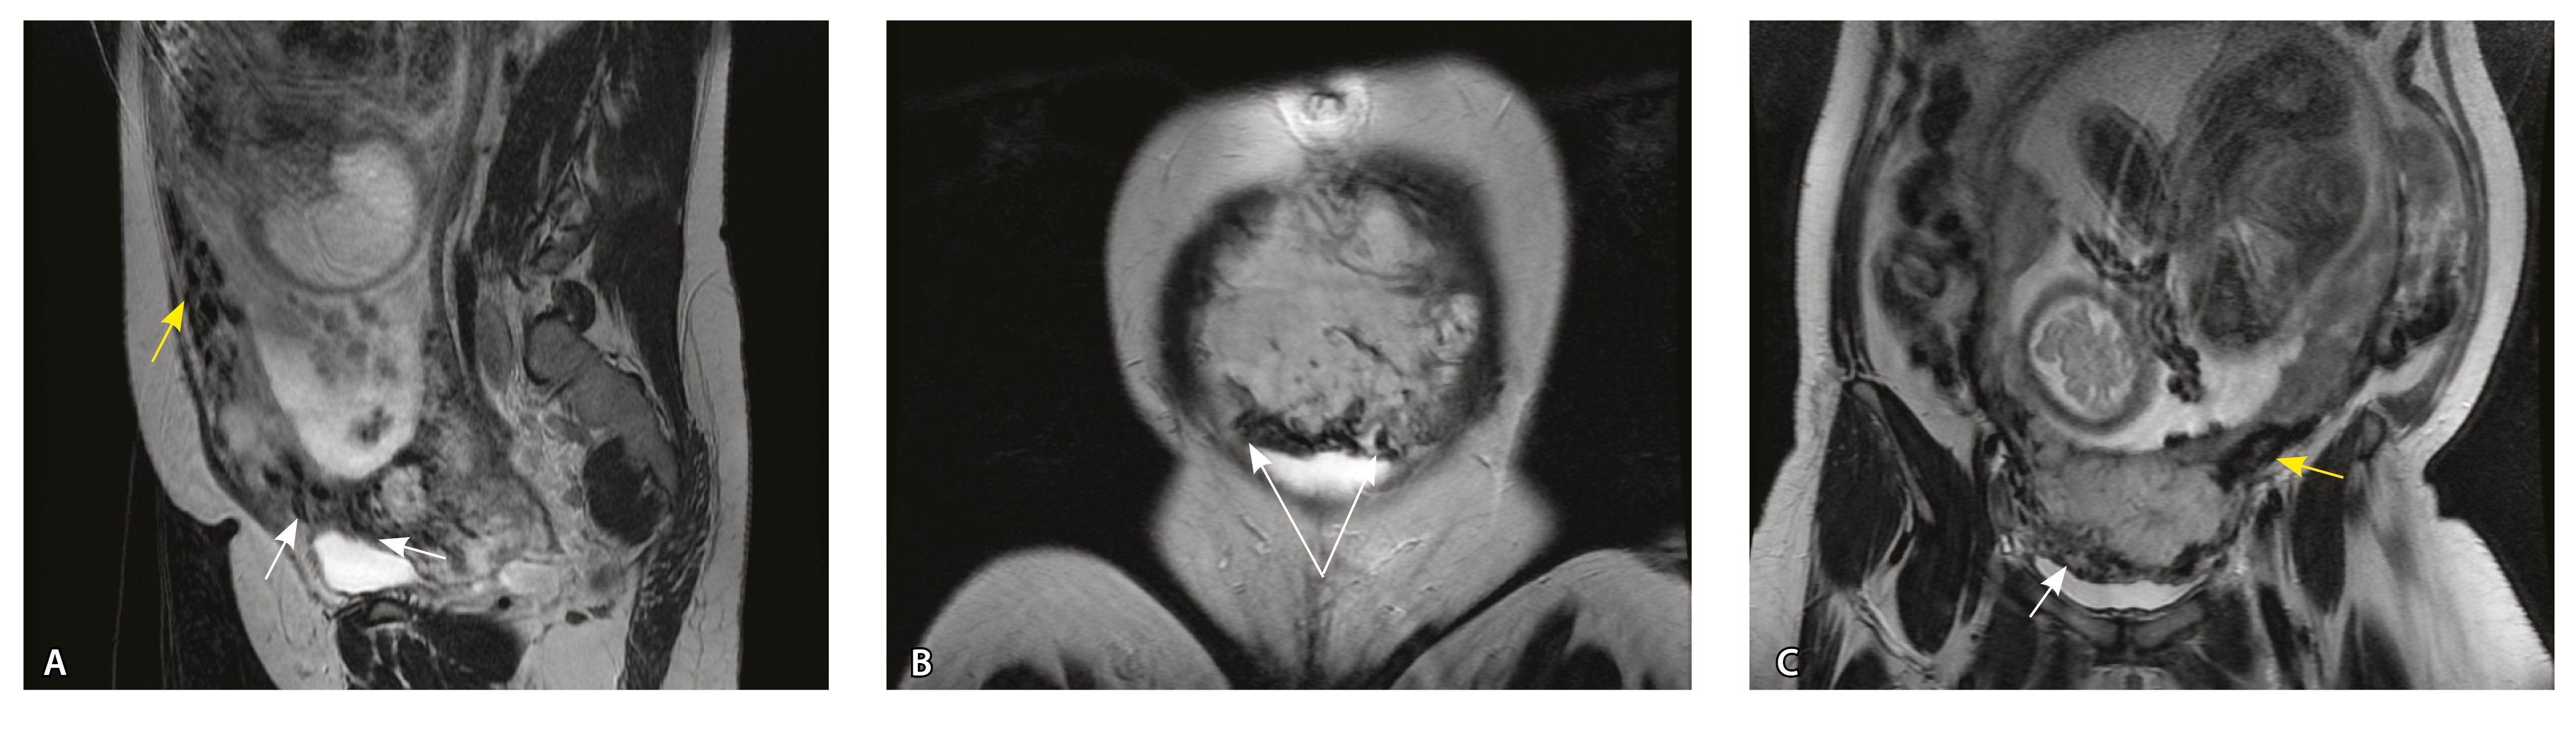

Рис. 4. Беременность 32 недели, pl. accreta, PAS 1 по FIGO. На магнитно-резонансных томограммах в режиме Т2-взвешенного изображения в сагиттальной (А) и аксиальной (Б) плоскостях видны сосуды на границе маточно-плацентарной области, сливающиеся между собой (белые стрелки), без выраженного дефицита толщины миометрия и рубца от кесарева сечения, без признаков выбухания стенки матки. На Т1-взвешенном изображении в режиме подавления сигнала от жировой ткани в аксиальной плоскости (В) выявляется наличие участков повышенного сигнала (желтые стрелки) на границе маточно-плацентарной области, что соответствует геморрагическому компоненту в подострой/хронической стадии (ретроплацентарные гематомы) либо белковому содержимому (фибриноид)

Непосредственное сравнение МР-картины с операционным материалом подтвердило, что полости с геморрагическим компонентом соответствовали ретрохориальным гематомам различной давности, чаще подострой и хронической стадий, которые состояли из гемолизированных эритроцитов, нитей фибрина сетчатого строения, а также замурованных атрофичных ворсин (рис. 5). Следовательно, констатация на МРТ фиксированных геморрагических полостей в маточно-плацентарной области отражает не гиперваскуляризацию стенки матки, а наличие ретрохориальных гематом в подострой/хронической стадии, что следует учитывать в клинической практике.